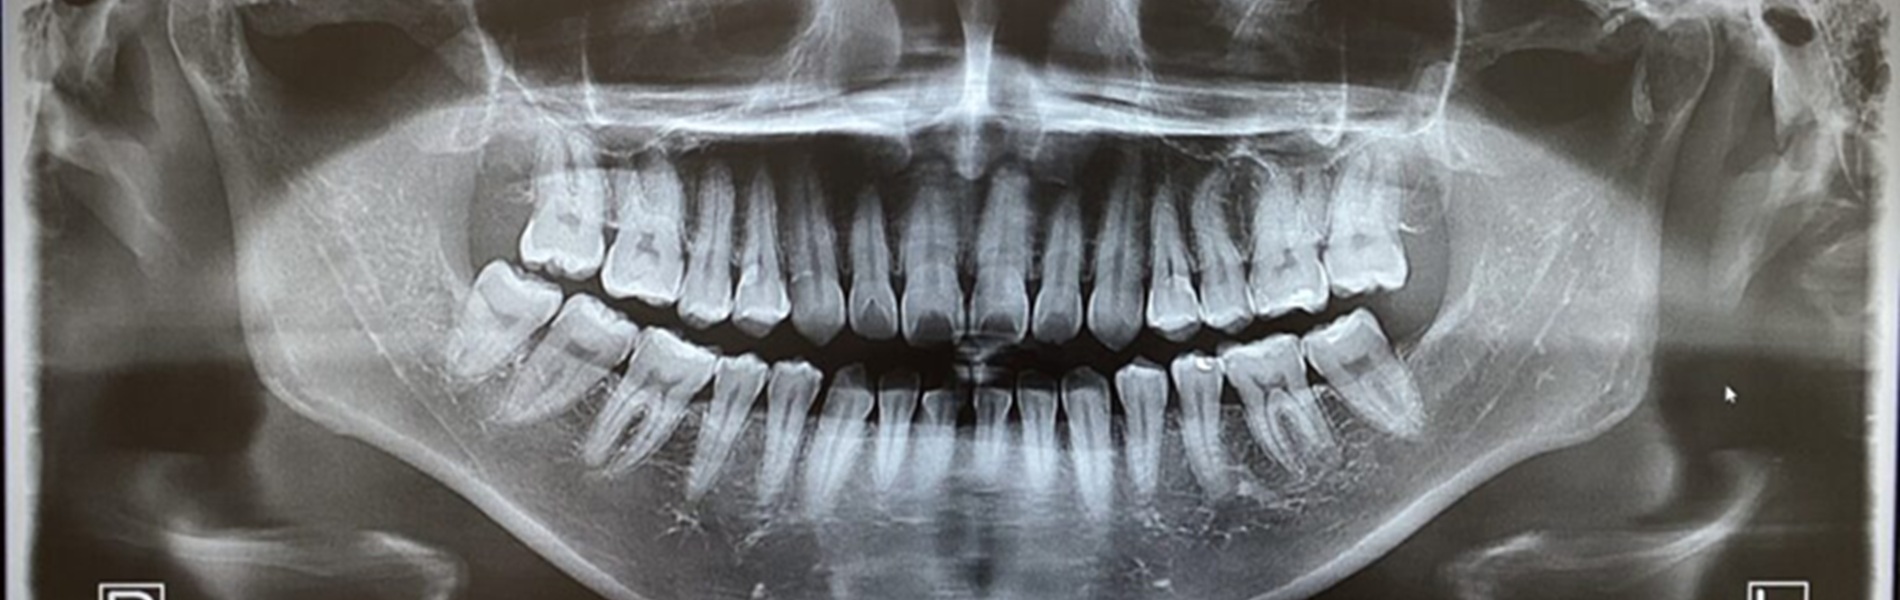

お口の状態をしっかり把握するために、必要に応じてレントゲン撮影や歯周病検査などを行います。これらの検査によって目に見えない虫歯や歯の根の状態、骨の健康状態まで確認します。